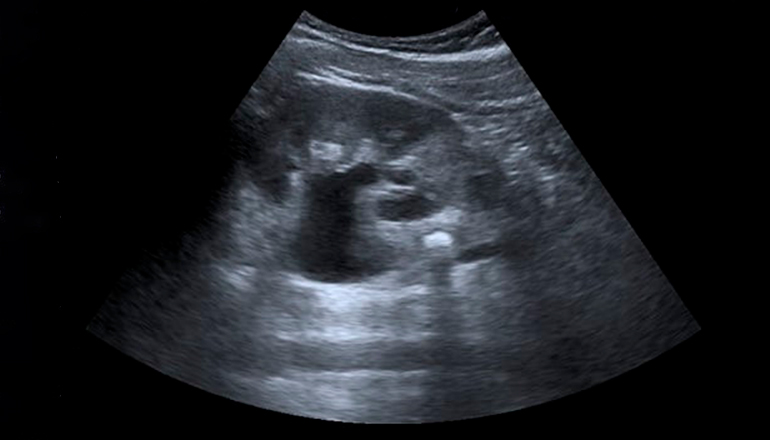

Ультразвуковое исследование почек — безопасный и эффективный способ диагностики, который позволяет врачам оценить состояние органа и выявить многие опасные патологии: от воспалений и камней до онкологии. Причем заметить нарушение можно даже на начальной стадии, когда симптомы еще не беспокоят, но патологический процесс уже запущен.

Заключение УЗИ почек на дому пациент получает сразу. Оно содержит описание состояния почек: их размер, форму, структуру и другие параметры. Если в ходе исследования были выявлены отклонения, следует обратиться к врачу и получить рекомендации по дальнейшему обследованию и лечению.